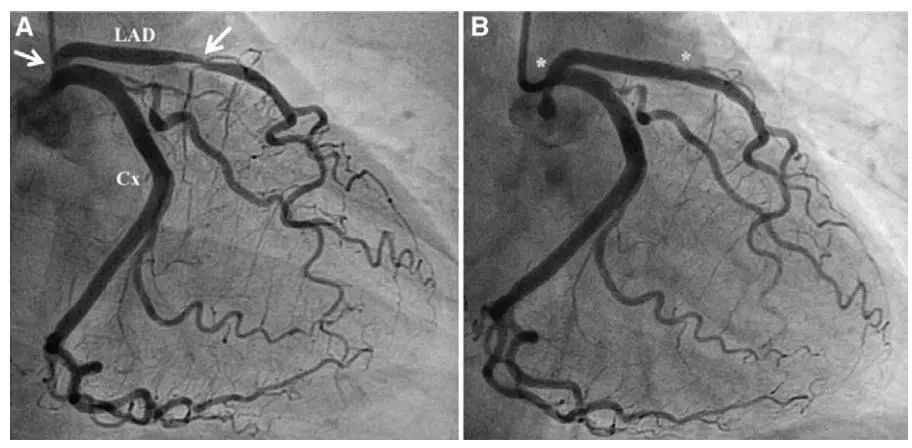

急诊冠脉造影示左前降支近段血栓形成并完全闭塞.